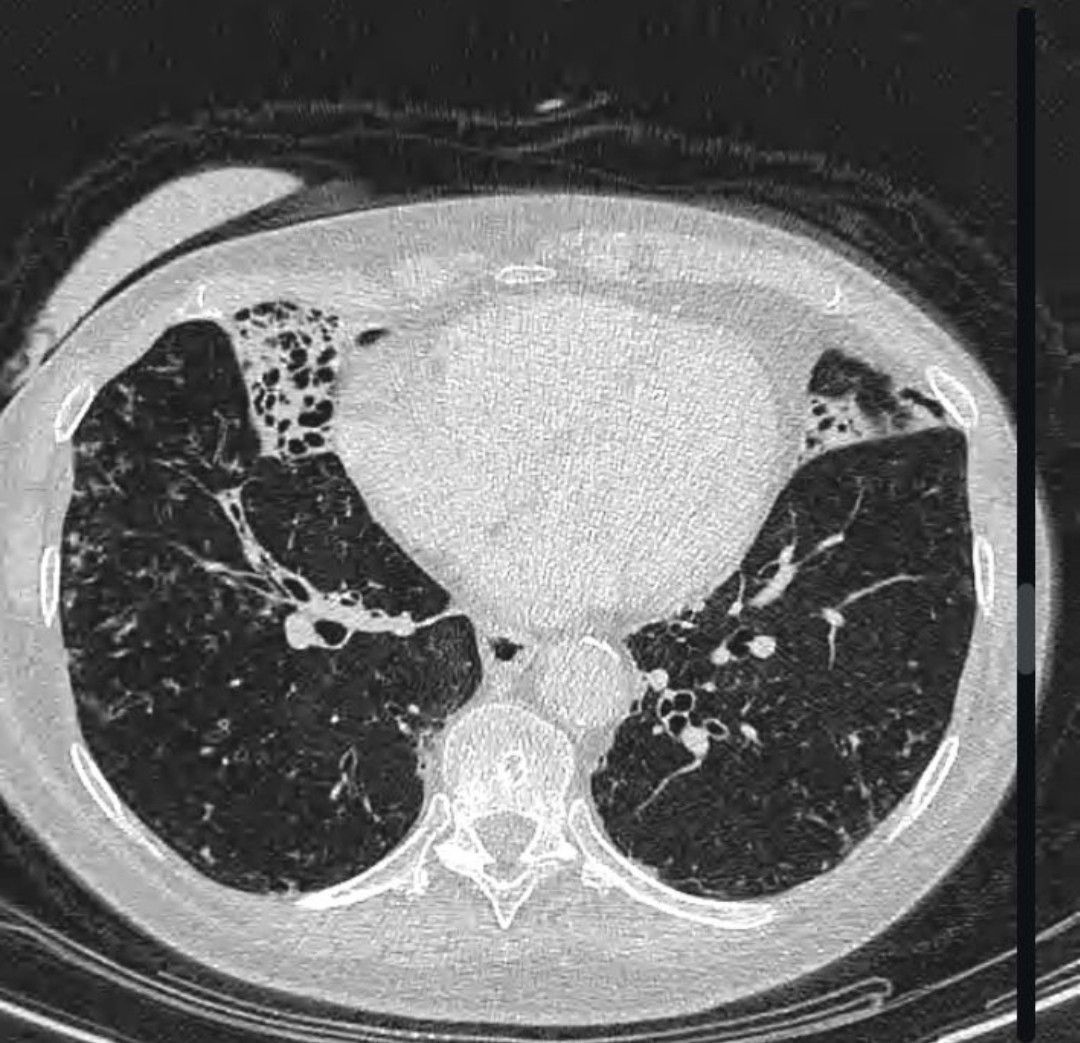

Extensive bronchiectasis and volume loss predominantly affecting the right middle lobe and the lingula segment of the left upper lobe. Bronchiectasis is also present at the lung bases. Centrilobular nodules and tree-in-bud nodularity are seen with basal predominance. Sputum was positive for Mycobacterium avium 5 years ago and the patient underwent antituberculosis treatment. This pattern of lung involvement (right middle lobe and lingula predominant) with bronchiectasis and volume loss is typical for Mycobacterium avium complex (MAC) infection.